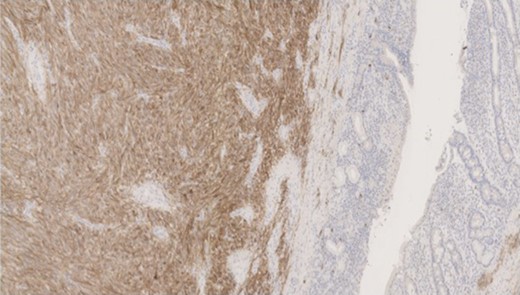

Pathology—GIST of spindle cell type (Figs 3 and 4), 90 mm in size, with complete local excision. Mitotic count—3 per 5 mm square. CD117 (Fig. 5) and DOG1 (Fig. 6) positive staining giving a prognostic group of moderate risk (Miettinen’s classification) of progressive disease. It is widely accepted that Interstitial Cells of Cajal (ICC) are pace maker cells of the gut and probable progenitor cells of GIST. Hyperplasia of ICC can be seen in cases with NF1, however, in this case this could not be shown in the background bowel (Fig. 7).

MNF staining the epithelium of the bowel while is negative in tumour cells.